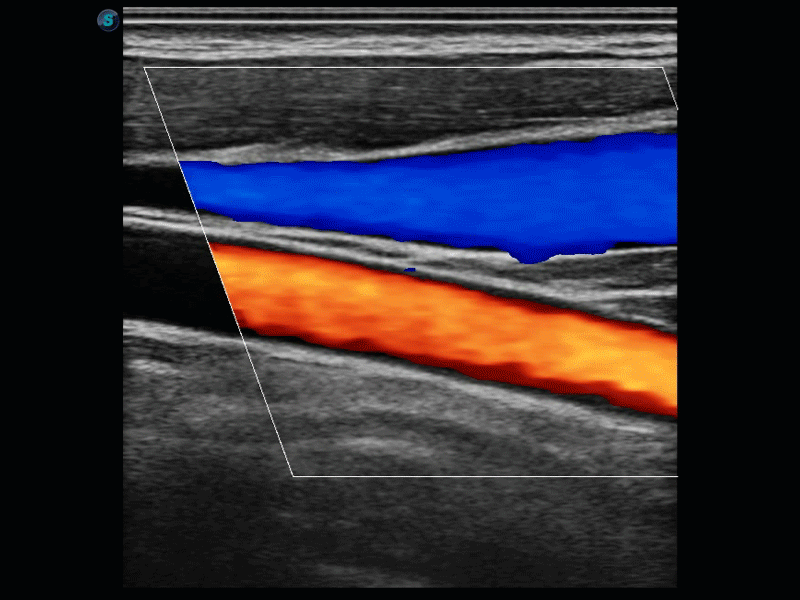

開立醫(yī)療通過不斷的技術(shù)創(chuàng)新,為大眾的生命健康提供持續(xù)關(guān)愛。P12 Plus采用全新一代超聲成像平臺,新平臺旨在將真實還原組織解剖結(jié)構(gòu)作為首要目標(biāo)。平臺采用全新集成化硬件模塊,搭載新一代芯片,系統(tǒng)性能得到大幅提升,為您的診斷提供了豐富的臨床信息。優(yōu)異的圖像表現(xiàn),豐富的探頭配置,全面的應(yīng)用功能,為您日常診斷提供了可靠的助手。

彩色多普勒超聲診斷系統(tǒng)